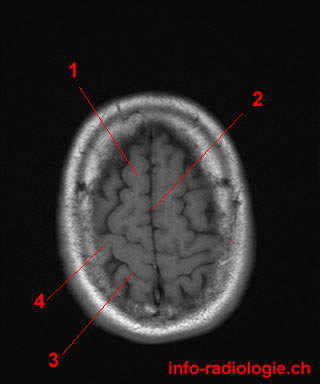

16. What is the name of the part of the brain responsible for motor functions?

The Precentral gyrus, also known as the primary motor cortex, is responsible for controlling voluntary movements in the body. It is located in the frontal lobe of the brain.

17. What is the part of the brain responsible for motor function?

The Central sulcus is located in the cerebral cortex and separates the frontal and parietal lobes. It plays a crucial role in motor function and is also known as the central fissure or fissure of Rolando.

18. What is the name of the ridge of the brain that lies between the frontal and parietal lobes?

The correct answer is the Superior frontal gyrus, which is a specific region of the brain located between the frontal and parietal lobes. This ridge is responsible for various functions related to motor skills, decision-making, and social behavior. While the other options provided are also structures within the brain, they do not specifically describe the ridge between the frontal and parietal lobes.